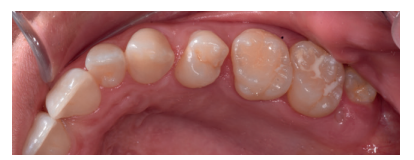

Caso clínico: se presenta un caso clínico de una mujer de 20 años, sin antecedentes médico-quirúrgicos de interés, que acudió a consulta remitida por su ortodoncista, para la extracción de un premolar maxilar retenido, en posición invertida. Tras la extracción del premolar y del tercer molar inferior retenidos, se obtuvo dentina procedente de ambos, para la regeneración ósea guiada del defecto resultante de la extracción del premolar, realizando revisiones a la semana y a los 4 meses de la intervención.

Clinical case: a clinical case of a 20-year-old woman is presented, with no interesting medical record, who went to dental clinic for removal of an inverse maxillary bicuspid retained. After maxillary bicuspid and lower third molar extractions, autogenous dentin was obtained from both teeth, to perform a guided bone regeneration of the bicuspid defect. A week and 4-month check-up were carried out.